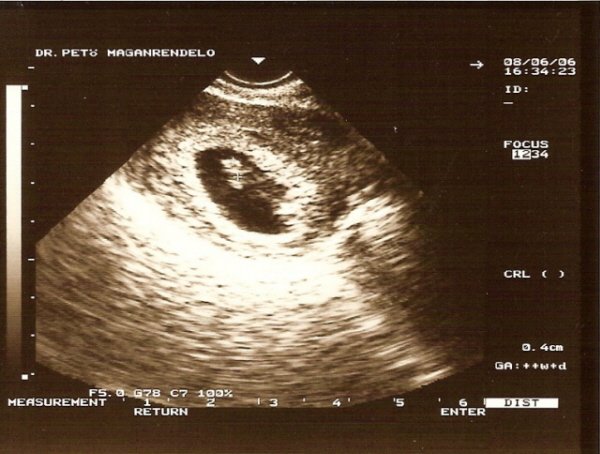

Addig felteszem Babó eddigi két sztárfotóját Nektek!!!

a>